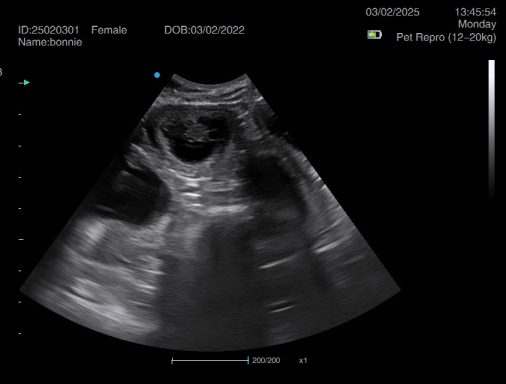

Ultrasound pregnancy scanning is a safe, non-invasive way to confirm pregnancy in dogs and cats, offering breeders and pet owners peace of mind and vital information to support responsible care. It allows us to detect gestational sacs, assess foetal development, and estimate litter size—all while ensuring the wellbeing of the animal.

Pregnancy can sometimes be detected as early as Day 18 post-mating, but scanning at this stage is not routinely recommended. Embryos are still developing and may not be clearly visible, and there is a natural risk of embryo resorption, which can lead to misleading or inconclusive results.

For the most accurate and reliable scan, we advise booking between Day 25 and Day 32, when pregnancy is more easily confirmed and foetal structures are clearer. If an early scan is performed and no pregnancy is detected, we offer a FREE complimentary re-scan after 7 days at the clinic to ensure clarity and support informed decision-making.

Our approach balances early insight with ethical care—always prioritizing the comfort of the animal and the accuracy of the results.

Gallery